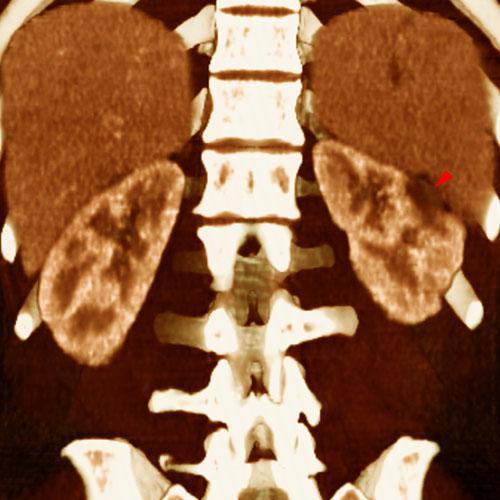

Infartos renales múltiples